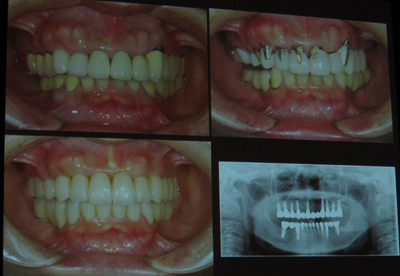

いつ見てもほれぼれする症例ばかりです。。。